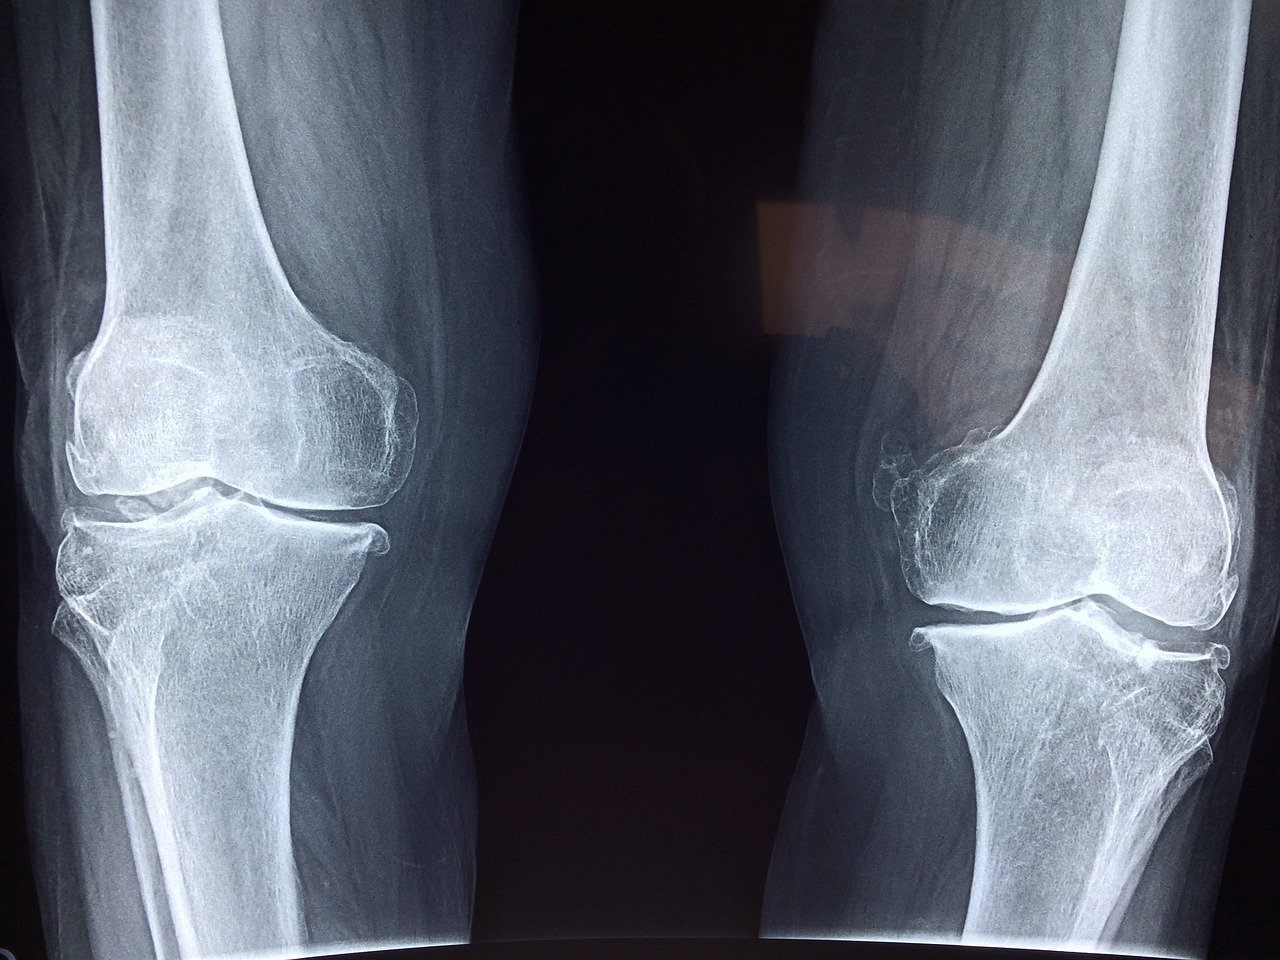

무릎 연골 질환은 무릎 관절의 연골에 영향을 미치는 다양한 상태들을 말합니다. 무릎 관절은 대퇴골(허벅지뼈), 경골(정강이뼈), 슬개골(슬개골)의 세 개의 뼈로 구성됩니다. 연골은 이 뼈의 끝을 덮고 있는 질기고 고무 같은 조직으로, 뼈가 서로 부드럽게 움직일 수 있도록 합니다. 또한 충격 흡수 장치 역할을 하여 마찰과 충격으로부터 뼈를 보호합니다.

첫째, 무릎 연골 질환의 가장 흔한 형태인 골관절염입니다. 이는 무릎 관절의 보호 연골이 시간이 지남에 따라 점차적으로 마모될 때 발생합니다. 골관절염은 노화, 과도한 관절 사용, 이전의 무릎 부상 또는 기타 요인으로 인해 발생할 수 있습니다. 종종 통증, 뻣뻣함, 부기, 이동성 감소와 같은 증상이 나타납니다.